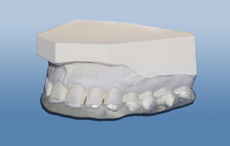

figur I

Bildet viser et eksempel på moderat tannslitasje som følge av tanngnissing.